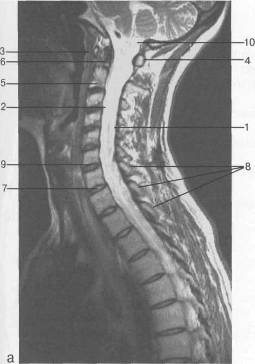

Рис. 14. МРТ. Парасагиттальное

изображение шейного отдела позвоночника. а-Т2-ВИ;б-Т1-ВИ.

- спинной мозг; 2 - субарахноидальное

пространство; 3 - передняя дуга С,; 4 - задняя дуга С,; 5 - тело Сп; 6 - зуб

Сп; 7 - межпозвонковый диск; 8 - дуги позвонков; 9 - гиалиновая пластинка; 10 -

большая цистерна.